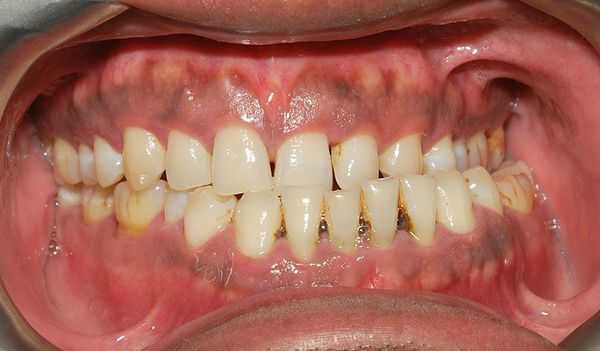

Пациентка Д. В., 26 лет. Диагноз: СЗЧЛА. Мезнальный открытый в переднем отделе прикус. Сужение зубных рядов. Тесное положение передних зубов.

Установлены элементы несъемной ортодонтической техники, сначала на верхний зубной ряд. Через полтора месяца — на нижний.

Через 11 месяцев пациентка была подготовлена к оперативному вмешательству. В течение двух последних месяцев были установлены стальные дуги максимального сечения (0,17x0,25).

В ходе коррекции за счет преимущественного использования прямоугольных дуг удалось избежать чрезмерной протрузии нижних передних зубов. Протрузия же верхних несколько уменьшилась за счет расширения верхнего зубного ряда.